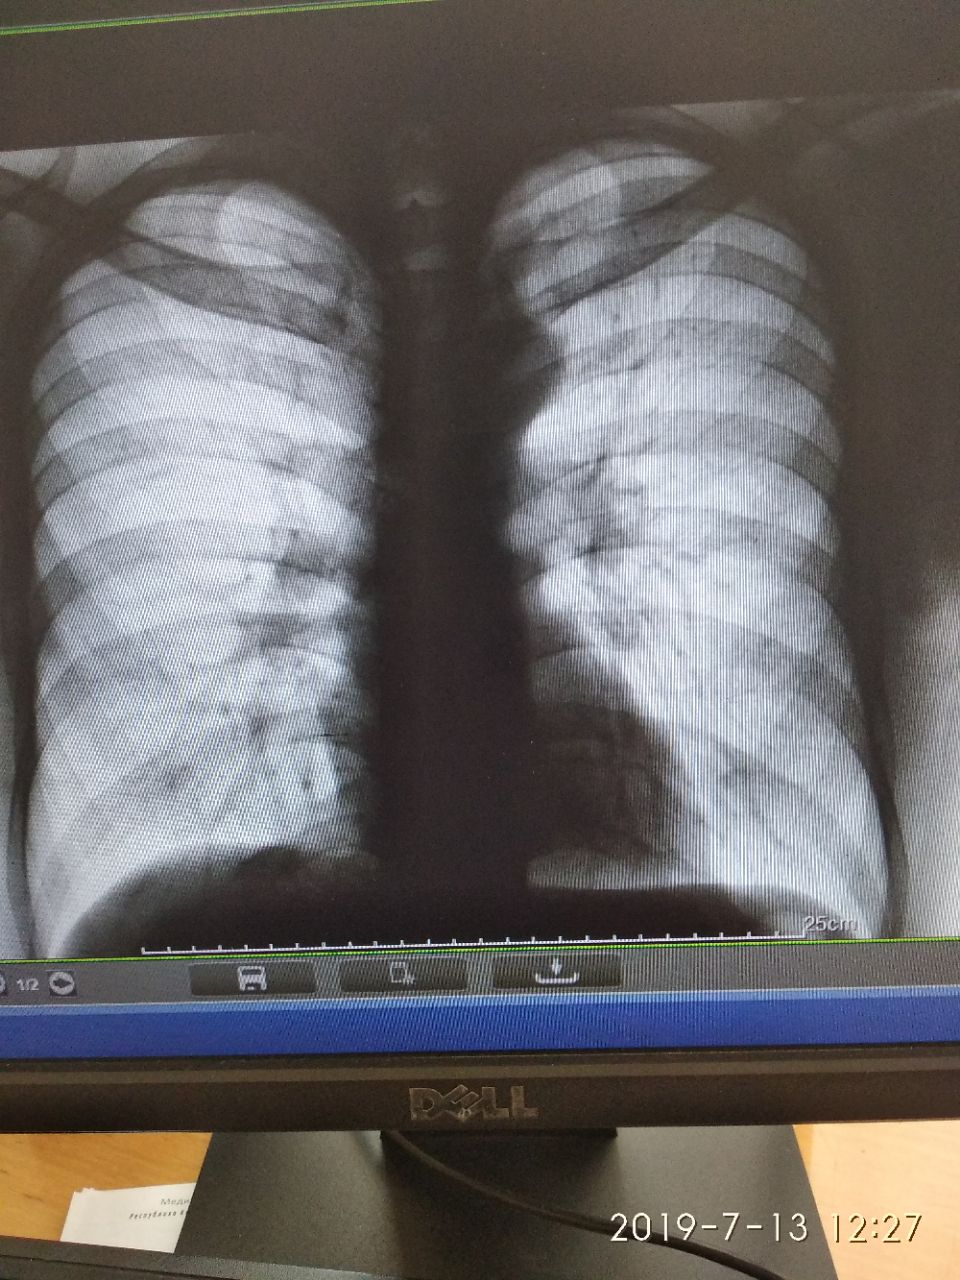

Нурланбек Усенов... in Radiology/Рентгенология Чатоид

источник

НУ

NL

Nikita Levin in Radiology/Рентгенология Чатоид

Клиника, анамнез, возраст

Что смущает

1997 г.р жалобы нет, туб анамнез отр

Слева верх отд